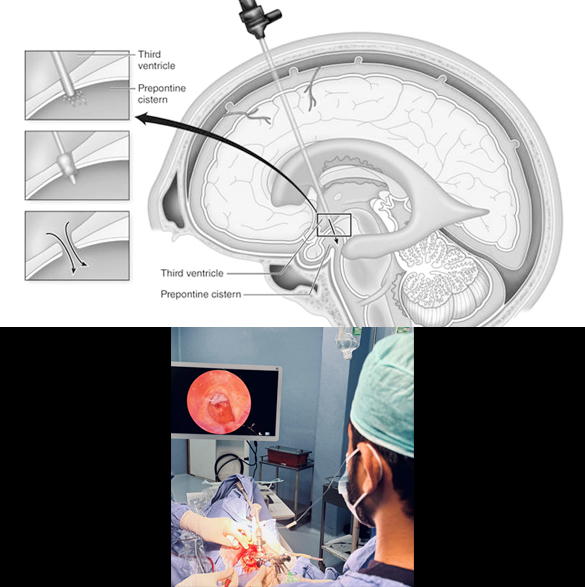

Endoscopic Third Ventriculostomy for Hydrocephalus

Endoscopic third ventriculostomy (ETV) is another type of surgical treatment for hydrocephalus where a neurosurgeon inserts an endoscope (a thin, lighted tube with a camera) through a small hole in the skull and into the brain's ventricles. It creates a diversion in the pathway of fluid (CSF) in the brain, with the help of an endoscope. ETV can prevent from placing a permanent catheter (VP shunt) in the brain. ETV is generally an elective procedure and can only be performed in some specific cases of hydrocephalus. It is usually avoided in emergency cases but can be performed even in infections. While ETV is a successful procedure for many, the success rate can vary depending on the cause of hydrocephalus and the patient's individual circumstances. Complications of this surgery may include wound infection, intracranial bleeding (failure to complete the procedure), and postoperative increasing hydrocephalus.